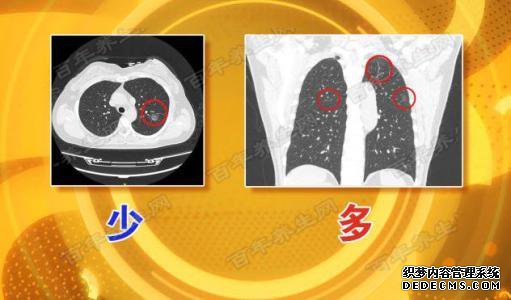

在临床上,根据CT图像显示的小肺结节的密度不同,将其分为纯毛玻璃结节,部分实性结节和实心结节。

其中,纯毛玻璃结节可能是常见的炎症,真菌感染,腺瘤样增生,上皮内腺癌,微浸润性或浸润性癌。一些固体,也称为混合磨玻璃结节,极有可能患癌症,并且需要身高。单纯的实性结节恶性可能性低,但是当其明显变恶性时,其相对恶性性就很高,并且进展迅速,因此在随访中必须谨慎。